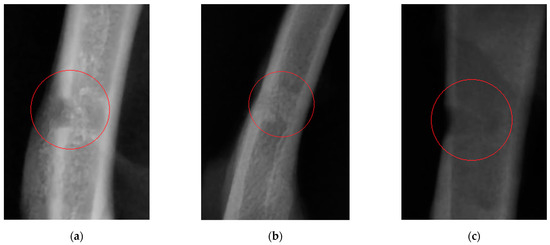

X-ray imaging on study day 21 (the time point at which femoral drilling was performed) clearly revealed the difference between bone tissue regeneration in the study and control groups (Figure 1).

Twenty-one days after the experiment start in Wistar rats (the time point when femoral drilling was performed and the analyzed feed supplements started to be received), the clinical condition of two rats in the control group worsened (as severely as bone fracturing in the defect area), while animals in the study groups did not have these complications. Partial ossification of osteoid tissue and the beginning of tubular bone structure restoration (in particular, cortical bone regeneration) were observed in study group 1. Complete regeneration of compact bone, full callus resorption, and activated bone structure restoration were revealed in study group 2 animals. A clear boundary of cortical bone restoration can be seen. The control group was characterized by incomplete restoration of the tubular bone structure and fragmentary replacement of the cartilaginous callus. The cortical bone was not restored; defect margins are well-marked. Consistent with the radiographic findings, morphological parameters of blood showed secondary erythrocytosis and thrombocytosis, which are typical of post-traumatic conditions in animals. In Wistar rats receiving the feed supplement simultaneously containing vitamin D and chelated silicon (group 2), unlike the same parameters in rats in study group 1 and the control group, the Ca/P ratio lay within the physiological range [33], which indicates that bone tissue regeneration was completed and mineral turnover in the body was normalized. The effectiveness of the diet containing the designed feed supplement has also been proved according to the reduced activity of alkaline phosphatase compared to that in the control group. The cortical thickness index in animals in the study groups on study day 21 was closer to the limits of the normal range, compared to this parameter in the control group. If the cortical thickness index is smaller than the normal value [29], it is fair to say that cortical bone thinning and calcium depletion has taken place. Hence, it has been demonstrated that the use of the supplements under study favorably affects calcium and phosphorus absorption from food and prevents bone decalcification during bone regeneration.

Figure 1. An X-ray image of the bone defect in rats on study day 21: (a) rats receiving the feed supplement containing silicon chelates; (b) rats receiving the feed supplement containing silicon chelates and vitamin D; and (c) rats receiving food without any supplements.